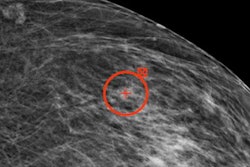

They looked at data from 14,768 Swedish women in the Malmö Breast Tomosynthesis Screening Trial. The average age of the women was 57 years. Of the 136 cancers found, 95 were detected on 2D digital mammography and 41 were detected only on DBT.

A cancer was defined as AI-detected if the cancer lesion was correctly localized and had a score of at least 62, the threshold determined by the software developers. If a score of 62 or higher was reached, the lesion was given the maximum examination risk score of 10.

The highest examination risk score was assigned to 1,493 breast exams, about 10.1% of the total patient cohort. The AI system detected 71 of the digital mammography-detected cancers. Of the cancers that radiologists detected on DBT only, 18 were detected by the AI system, 17 of which were invasive.

Despite AI's inferiority to double reading, the system also identified relevant findings missed by the radiologists. The researchers said a "substantial" number of DBT-only detected cancers and interval cancers were missed by human readers but were correctly identified by AI on digital mammography.